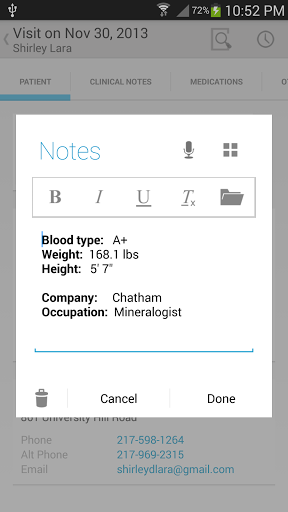

• Pendant les visites des patients, ajouter des notes de visite / médicales comme du texte, une image, un enregistrement vocal ou une écriture manuscrite

• Utiliser la dictée pour écrire automatiquement du texte sur des notes médicales

• Outil puissant intégré pour aider à gérer les notes réutilisables